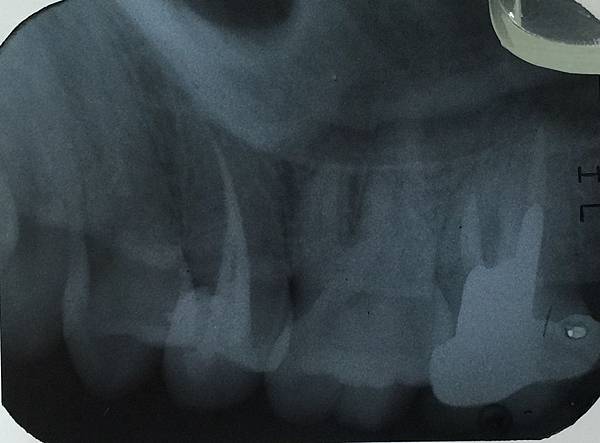

從外觀看完全沒有蛀牙的跡象

也沒有疼痛的症狀 於是我們上麻藥之後

把牙齒打開

果跟X光片顯示的一樣 是一個大蛀牙

當把蛀牙清乾淨時 就會傷到神經

這就是為什麼

[牙齒不會痛卻要抽神經]的原因了

於是我們把蛀牙清乾淨

裡面正如X光顯示蛀到神經

開始根管治療

用牙科用銼針將牙齒內部的神經組織清乾淨

確認神經管長度與治療長度一致